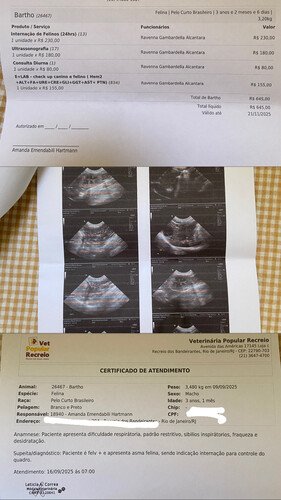

Oi pessoal! Eu sou a Amanda, mãe do Bartho, meu filho pet. Barthozinho está passando por uma fase bem difícil. Ele tem felv (leucemia felina), tem asma, recentemente descobrimos uma úlcera no olhinho que ainda está em tratamento mas já sabemos que perdeu parte da visão e agora os veterinários suspeitam de uma encefalite, que é a inflamação do cérebro, provavelmente causada pela felv. Ele já foi internado duas vezes esse ano, em setembro e agora em outubro, e ainda não teve alta.

Acontece que Barthozinho está com a coordenação motora debilitada, tem dificuldade para andar, subir/descer dos lugares, se limpar, ir ao banheirinho fazer suas necessidades e até comer. Nesse momento ele está completamente dependente de mim. E para termos o diagnóstico preciso e iniciar o tratamento o quanto antes, precisamos fazer dois exames no qual eu não tenho condições financeiras de arcar, visto que já gastei mais de R$ 4.000 com todas essas internações, medicamentos e exames. Esses dois exames necessários são a ressonância magnética e o exame de líquor, que é a retirada de um líquido do crânio para diagnosticar doenças neurológicas, como infecções (meningite, encefalite), inflamações e tumores no sistema nervoso central.. Esses dois exames ficam em torno de R$ 6.000 e pensando em todas as possibilidades de conseguir essa grana, eu criei essa vaquinha online.